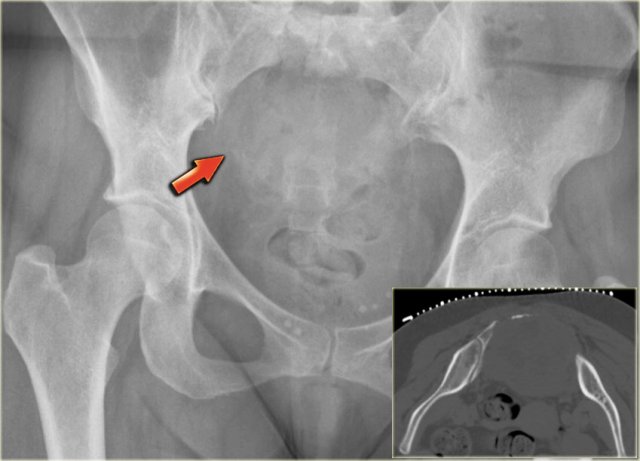

On the left a patient with a chondrosarcoma of the right acetabulum.

On the CT expansion and subtle calcifications are present.

On the coronal T2-weighted image the tumor is seen as a large lobulated mass with very high SI, which is typical for chondroid tumors.

The T1-weighted image after Gd shows typical peripheral nodular enhancement.

In the center there is no enhancement.

This is probably due to a large myxoid component. .